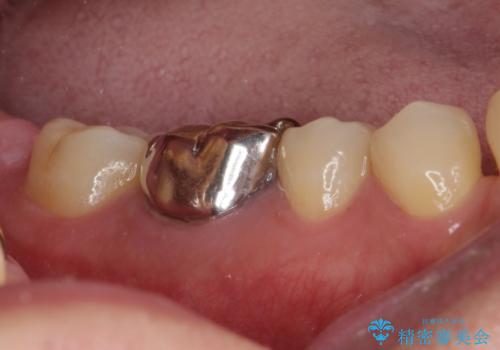

奥歯の目立つ銀歯が気になる 奥歯のセラミッククラウン

- 口を開けたときに目立ってしまう銀歯をセラミックに替えたいとのことで来院された患者様です。

以前むし歯治療を受けたときは時間がなかったため、近医で銀歯を入れたようですが、周囲の目線が気になるとのことでフルジルコニアクラウンにて補綴することとしました。